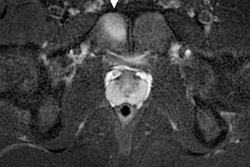

Based on data from previous summer Olympics, he said he anticipates that around 1,860 scans will be performed on the 10,400 or so competitors from 206 nations. Renoux, who works as a musculoskeletal (MSK) radiologist at France’s National Institute of Sport, Expertise, and Performance (INSEP), estimates that 900 MRI exams, 600 ultrasound scans, 300 x-rays, and 60 CTs will be carried out during both the Olympics (26 July to 11 August) and the Paralympics (28 August to 8 September).

The imaging department at the polyclinic will be equipped with two mobile MRI scanners (Ingenia, from Philips), three ultrasound machines (Aplio i800, from Canon), and one x-ray system (from Primax International). In addition, a mobile CT unit will be located outside the Olympic Village, next to the velodrome for cycling.